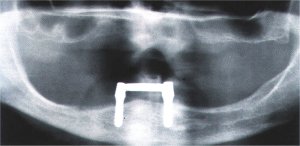

Zahnloser Unterkiefer mit zwei Implantaten versorgt.

Fall Nr. 3

In günstigen Fällen können die Implantate bereits nach einer Einheilzeit von 6 Wochen mit Verbindungselementen versehen werden, die eine Steg- / Gelenk- Konstruktion aufnehmen.

Sicherer Halt der Unterkieferprothese wird über viele Jahre gewährleistet, Fortschreiten des Kieferknochenabbaus entscheidend verzögert.